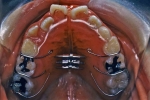

ベッグタイプ

抜歯症例の場合、抜歯した部分が後戻りして隙間が生じるのを防止するため歯並び全体を包み込むように、ワイヤーが取り囲むデザインの保定装置が使用される場合があります。このデザインをベッグタイプのリテーナーと言います。